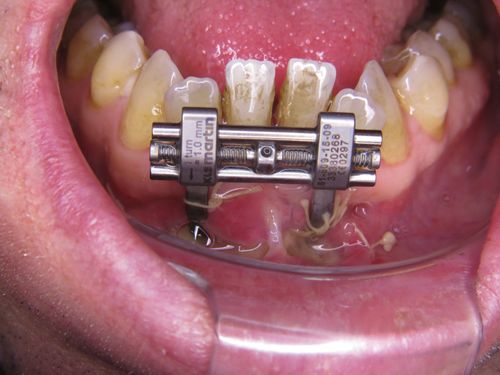

In einem ersten Behandlungsschritt wurden Ober und Unterkiefer verbreitert (transversaler Erweiterung). Allein dadurch zeigte sich schon eine Verbesserung der Atmung im Schlaf.